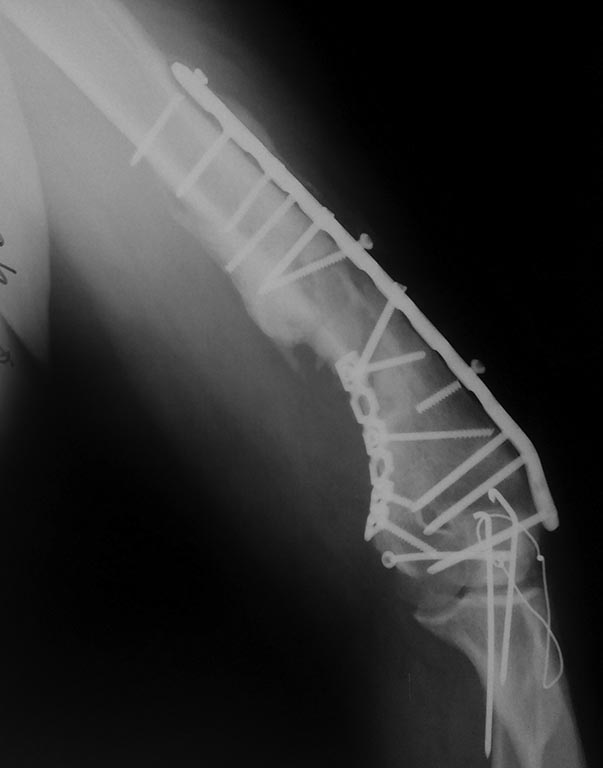

[Ortho] Реостеосинтез плеча. Что дальше...?

"первичный" снимок